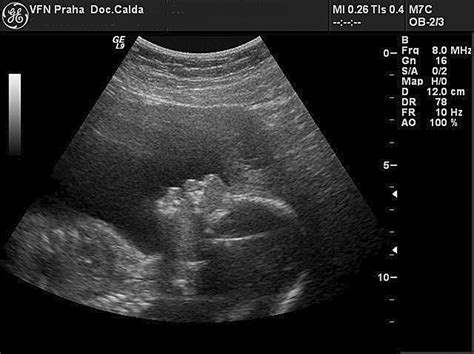

NT (Nuchal Translucency) - šijové prejasnenie je definované ako nahromadenie tekutiny v zátylku plodu na konci prvého a na začiatku druhého trimestra. Pri plodoch s Downovým syndrómom, s genetickými anomáliami, vážnymi chybami srdca a hrubých ciev alebo skeletálnymi dyspláziami sa na tomto mieste nachádza väčšie množstvo tekutiny, čo spôsobuje edém záhybu šije. Ten sa prejaví vysokými hodnotami NT. Hrúbka šijového prejasnenia je u zdravých plodov cca 1 až 2,5 milimetra (norma až do 3 mm).

Vyšetrenie sa musí vykonať v 11. až 13. týždni tehotenstva, presné stanovenie veku gravidity je základným predpokladom relevantného výsledku. Je rozdiel v hodnotách NT aj pre tieto tri týždne. Zároveň je pri meraní dôležitá poloha plodu (neutrálna), iná poloha hlavičky môže výsledky skresliť. Keďže sa jedná o veľmi presné meranie s malou toleranciou odchýlky (desatiny milimetra), štúdie potvrdzujú, že toto vyšetrenie môže urobiť len vyškolený sonografista s kvalitným ultrazvukom.

V 18. týždni musí byť dĺžka nosnej kosti nad 2,5 mm, ale v priemere sa pohybuje okolo 4-5 mm. Vyšetrenie nosovej kosti je niekedy limitované polohou plodu a sklonom tváre voči ultrasonografickej sonde. Ideálne podmienky na meranie sú vtedy, ak je plod otočený tvárou k sonde a pozdĺžna os nosovej kosti a USG vlnenie tvoria 90 stupňový uhol.